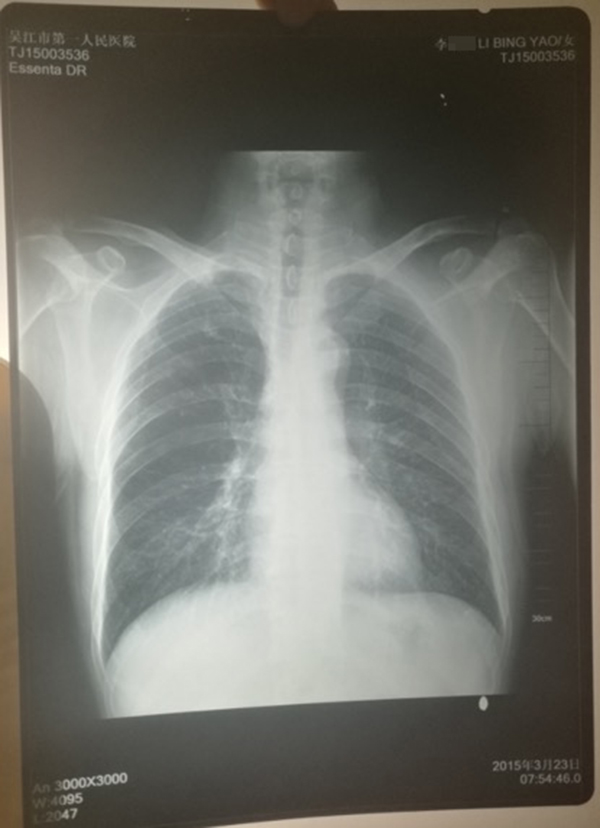

醫(yī)院提供的計(jì)建宏的“真實(shí)胸片”,寫有姓名“李某某”。 受訪人供圖

計(jì)云強(qiáng)稱,吳江區(qū)第一人民醫(yī)院曾提供一份印有“李某某”姓名的胸片,并稱該胸片才是計(jì)建宏的“真實(shí)影像結(jié)果”。

對(duì)于“李某某”姓名的胸片,上述吳姓主任稱,經(jīng)過醫(yī)院核查,兩份胸片的結(jié)果都是“正!钡,“如果結(jié)果是不一樣的話,那么問題就大了,但是因?yàn)槭且粯拥慕Y(jié)果,所以不能認(rèn)為是‘漏診’或‘誤診’!

對(duì)于醫(yī)院的回應(yīng),計(jì)云強(qiáng)認(rèn)為醫(yī)院是將皮球踢給了患者,并對(duì)醫(yī)院解決事情的態(tài)度不滿,同時(shí)還對(duì)醫(yī)院提供的印有“李某某”姓名的父親胸片真實(shí)性存疑,“醫(yī)院應(yīng)該主動(dòng)去證實(shí)片子是我父親的!